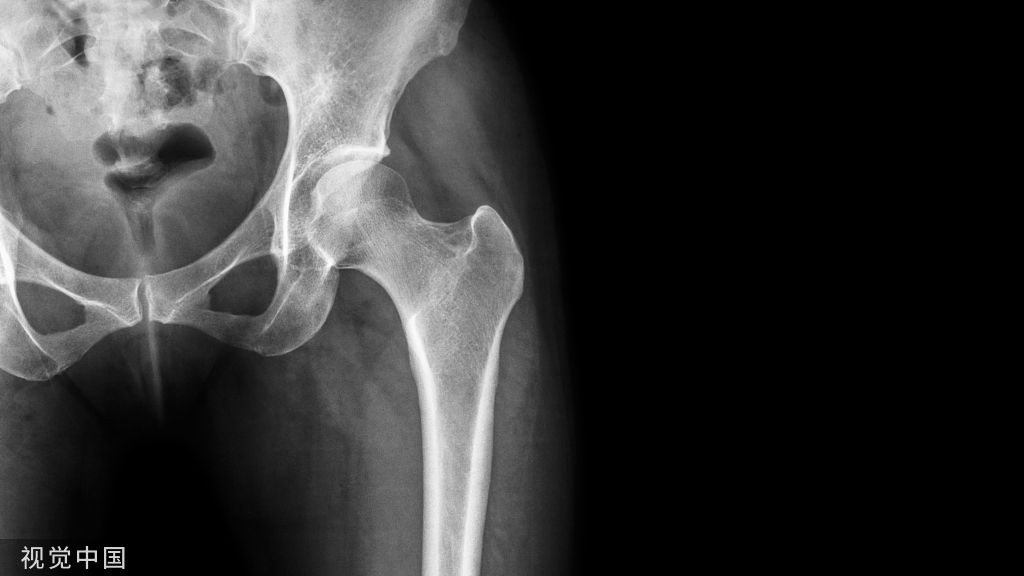

闭孔斜位片:(重点观察前柱、后壁)

髂骨斜位片:(重点观察后柱、前壁)